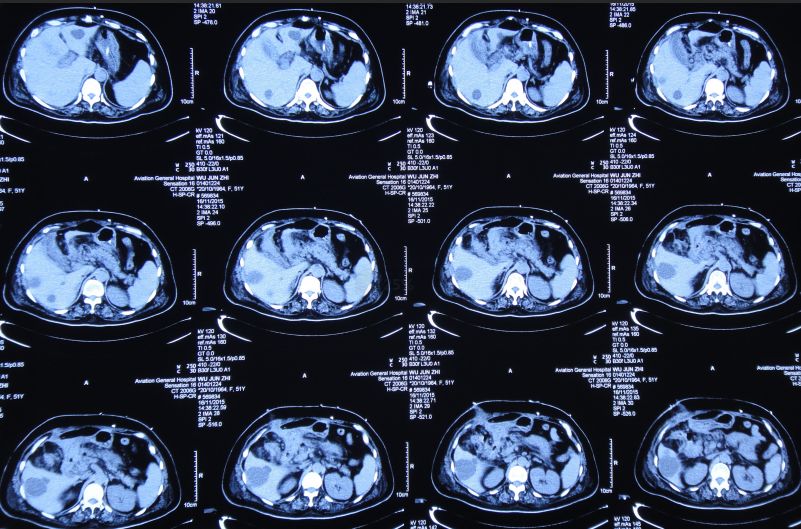

当日上午患者诉上腹部、下胸部疼痛。急查腹部CT:肝内多发囊肿;胆囊结石、胆总管结石(图32)。

![]()

图32:2015年10月27日腹部CT肝内多发囊肿;胆囊结石、胆总管结石

因两次心肌酶检查无明显变化,心内科会诊:基本可排除心肌梗死,但考虑患者有轻度冠心病可能。患者神清,精神差,呼吸急促,间断呕吐、腹痛。普外科会诊:考虑患者有胆囊结石、胆总管结石,目前症状与此有关,可采取保守治疗或手术治疗。与家属沟通后,决定暂给予抗感染、补液等保守治疗。